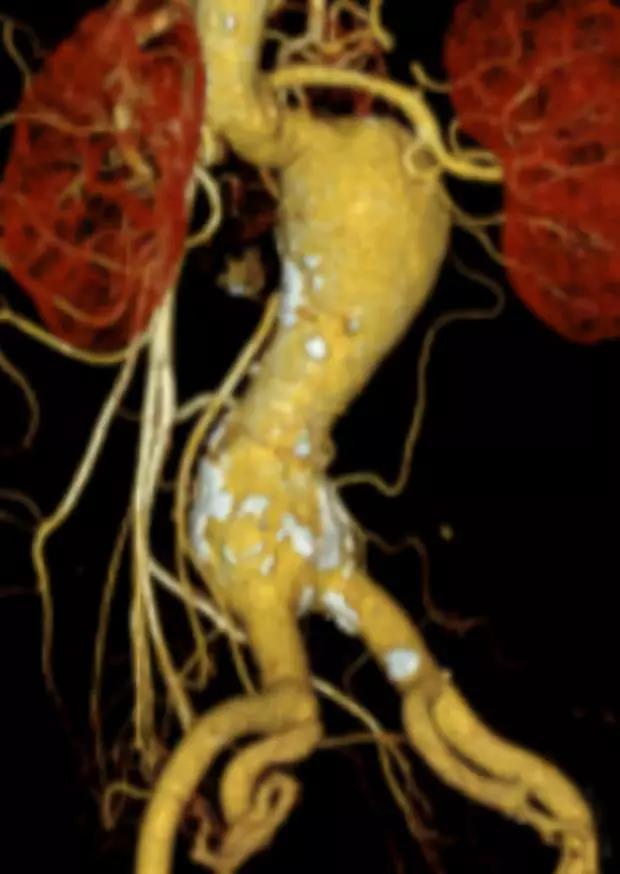

此次研究,纳入腹主动脉瘤的最大直径为85mm,平均直径为50.78mm;最短瘤颈长度为11mm,平均长度为31.34mm;最大肾下成角为74.6度,平均角度为32.48度。从动脉瘤最大直径变化来看,经过腹主动脉腔内治疗后,在出院前和术后6个月都有所减小。 在此次研究中,先健Yuranos™新一代腹主动脉覆膜支架系统临床试验初步展现了优秀的临床试验结果,其30天内MAE发生率低,安全性得以验证;而且由于该产品的柔顺性有较大提升,输送器直径减小,对于短瘤颈和角度大的病例是更好的选择。 入组病例展示: 病例一:男性,年龄69岁,既往高血压,糖尿病病史。术前腹主动脉瘤直径67.3mm,近端瘤颈长度23.2mm,近端锚定区直径21.2mm,肾下成角60.5度。 术中从右侧股动脉穿刺,选用先健型号为AB-2412-50-120的主体支架,支架近端定位于右肾动脉开口处,后释放打开裸支架,并向下释放主体短分支,左侧输送进入先健髂动脉延长支架IE-1416-100,并释放,保留左侧髂内动脉。接着释放主体长分支,右侧输送进入先健髂动脉延长支架IE-1424-80,并释放,保留右侧髂内动脉。 手术顺利,无内漏,持续时间1小时10分钟。术后CTA检查,支架形态良好,无内漏。详见下图: 术前影像 术中影像 出院前影像 术后6个月影像 术后1年影像 病例二:女性,年龄72岁,既往高血压,静脉曲张病史。术前腹主动脉瘤直径48.81mm,近端瘤颈长度16.15mm,近端锚定区直径18.43mm,肾下成角66度。 术中从右侧股动脉穿刺,选用先健型号为AB-2412-50-140的主体支架,支架近端定位于右肾动脉开口处,后释放打开裸支架,并向下释放主体短分支,左侧输送进入先健髂动脉延长支架IE-1414-120,并释放,保留左侧髂内动脉。接着释放主体长分支,右侧输送进入先健髂动脉延长支架IE-1414-80,并释放,保留右侧髂内动脉。